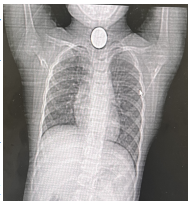

当救护车抵达阿坝州人民医院时,耳鼻喉医师甯杰早已严阵以待,迅速接诊。他第一时间使用直达喉镜检查后发现孩子已经出现喉头水肿迹象,因恐慌无法继续配合检查,医师当机立断,结合CT影像学检查进一步诊断,结果令人倒吸一口凉气:硬币紧贴大血管!要知道,食管入口被颈部最重要的“血管丛林”所包绕,尤其是左侧的颈总动脉和后方跨越的主动脉弓分支,稍有不慎,硬币的移动就可能划破血管,引发大出血,后果不堪设想。